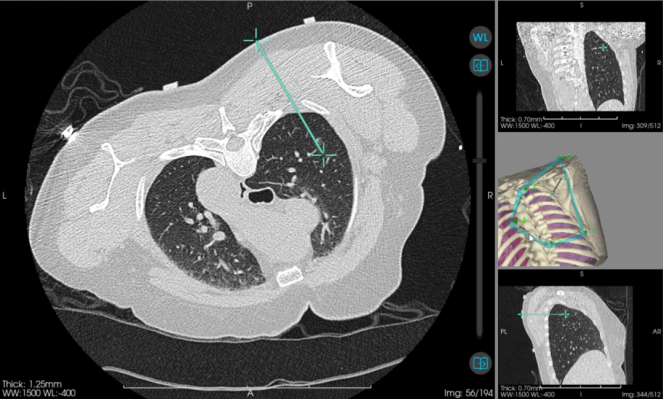

图为机器人引导下实际穿刺路径。广西医科大学第一附属医院 供图

当天,该院心胸外科主任阳诺带领消融团队开展手术。他介绍,在术前,穿刺手术机器人系统基于患者CT影像,能自动构建详细的肺部3D立体模型,清晰呈现结节与周围血管、气管等重要组织的位置关系。

“它就像一位‘智能导航员’,精准规划穿刺路径、角度与深度,有效避开血管、气管等重要组织结构,将误差控制在毫米级。”阳诺说。